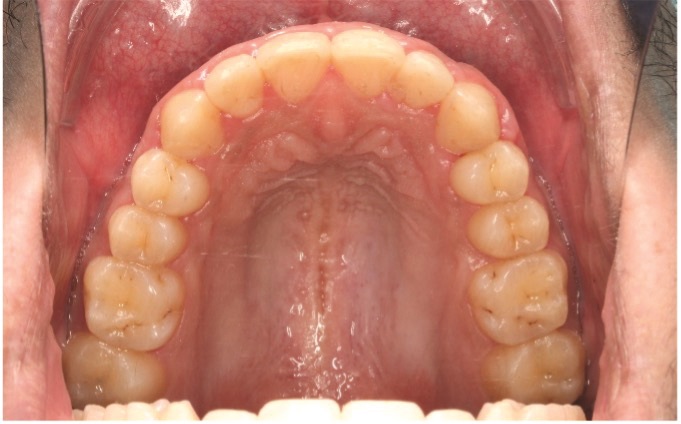

On the 13th visit, 17 months into treatment, upper and lower fixed appliances were debonded, and a lower 3–3 fixed wire retainer (Ortho FlexTech, Reliance) was installed. Soft and hard tissue were contoured, the embrasure touched up and gingiva on upper anterior teeth trimmed. The patient was supplied with polycarbonate retainers for both arches to wear at night (Figs. 9a–9h).